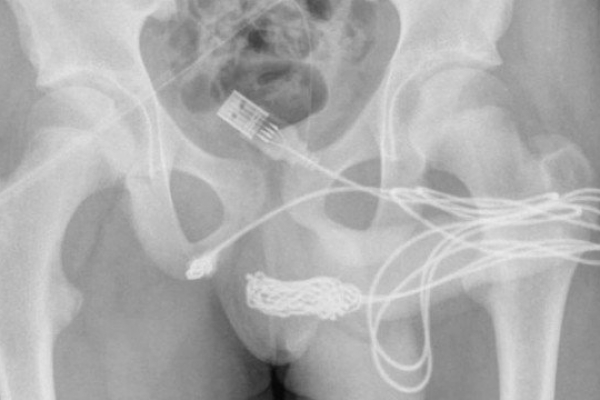

Adolescente é operado após tentar medir o pênis com um cabo USB